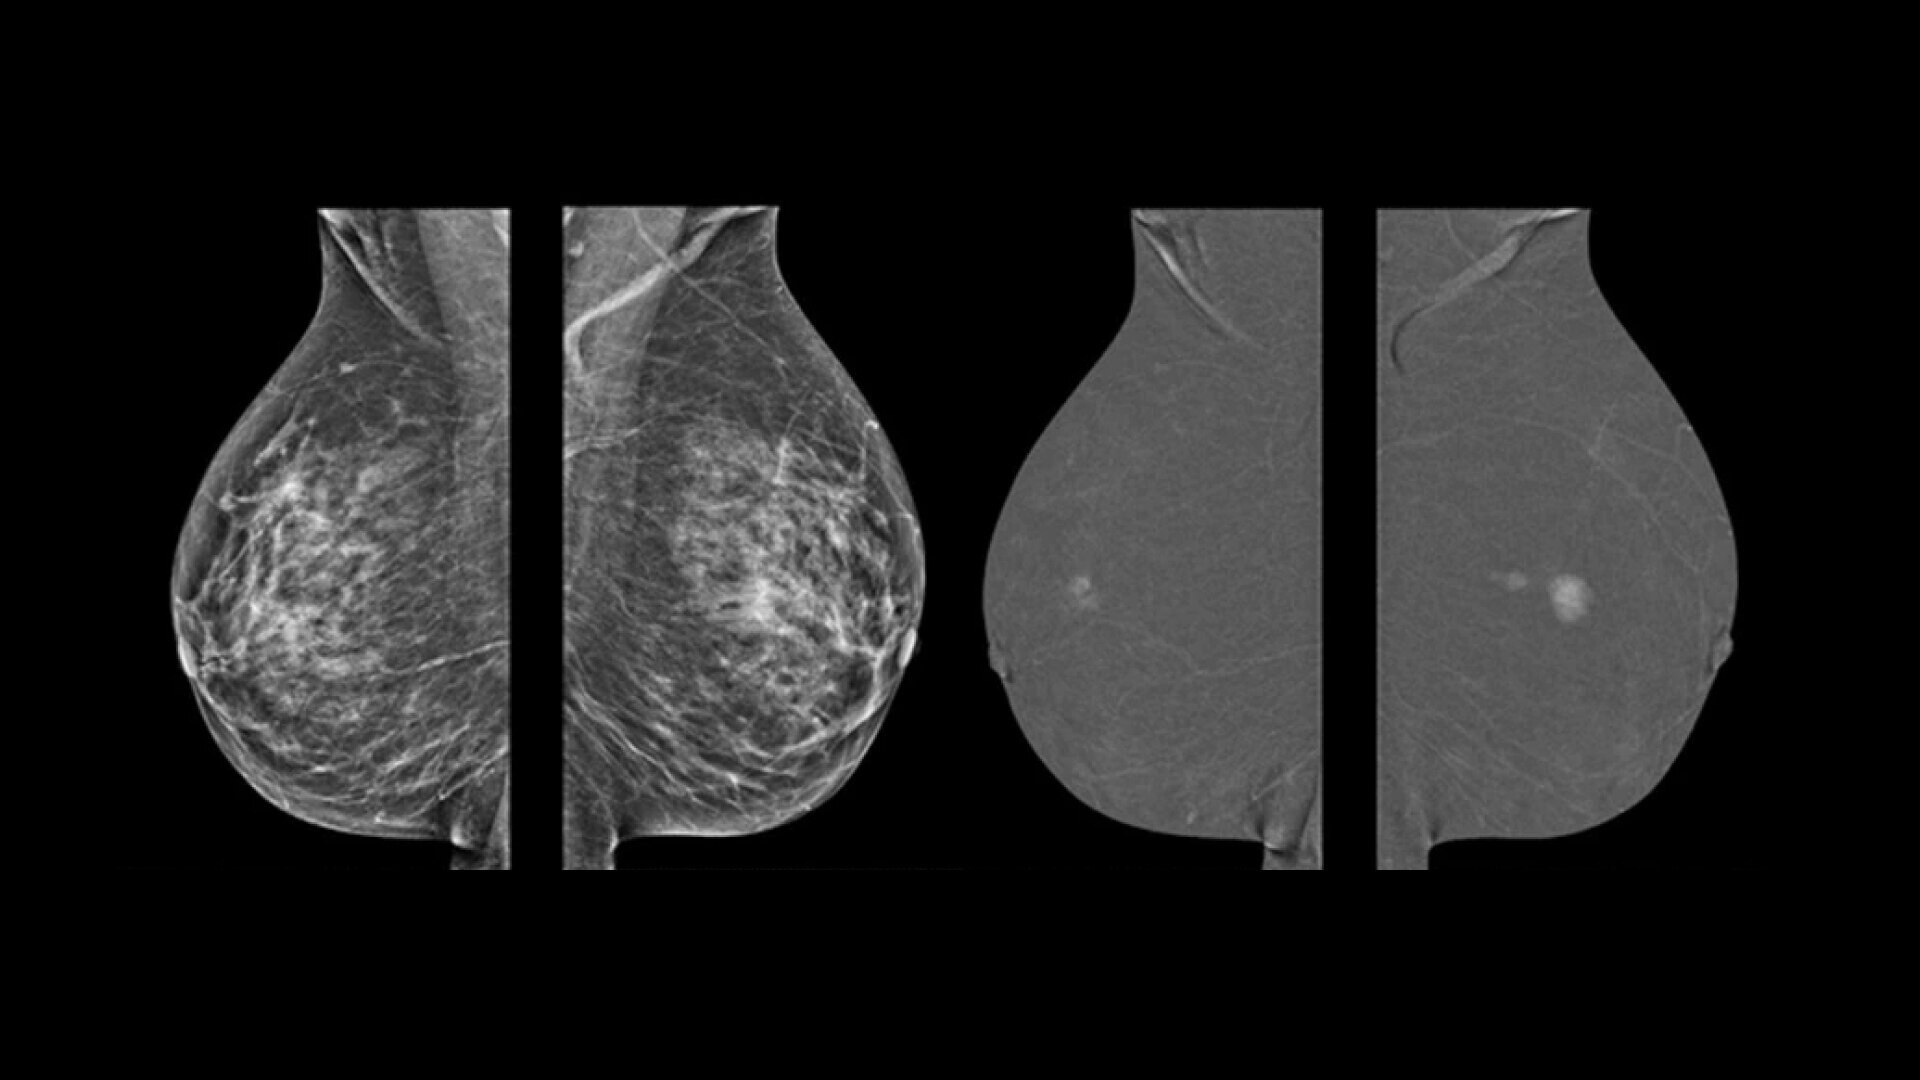

Astonishing clarity

The image you need is never out of reach

• Helps reduce the masking effect of fibroglandular breast tissue and increases the tumour signal1.

• Contrast agent highlights areas of unusual blood flow.

• CEM is an alternative imaging method to MRI, especially when MRI availability is limited, and for patients for whom MRI is contraindicated5.